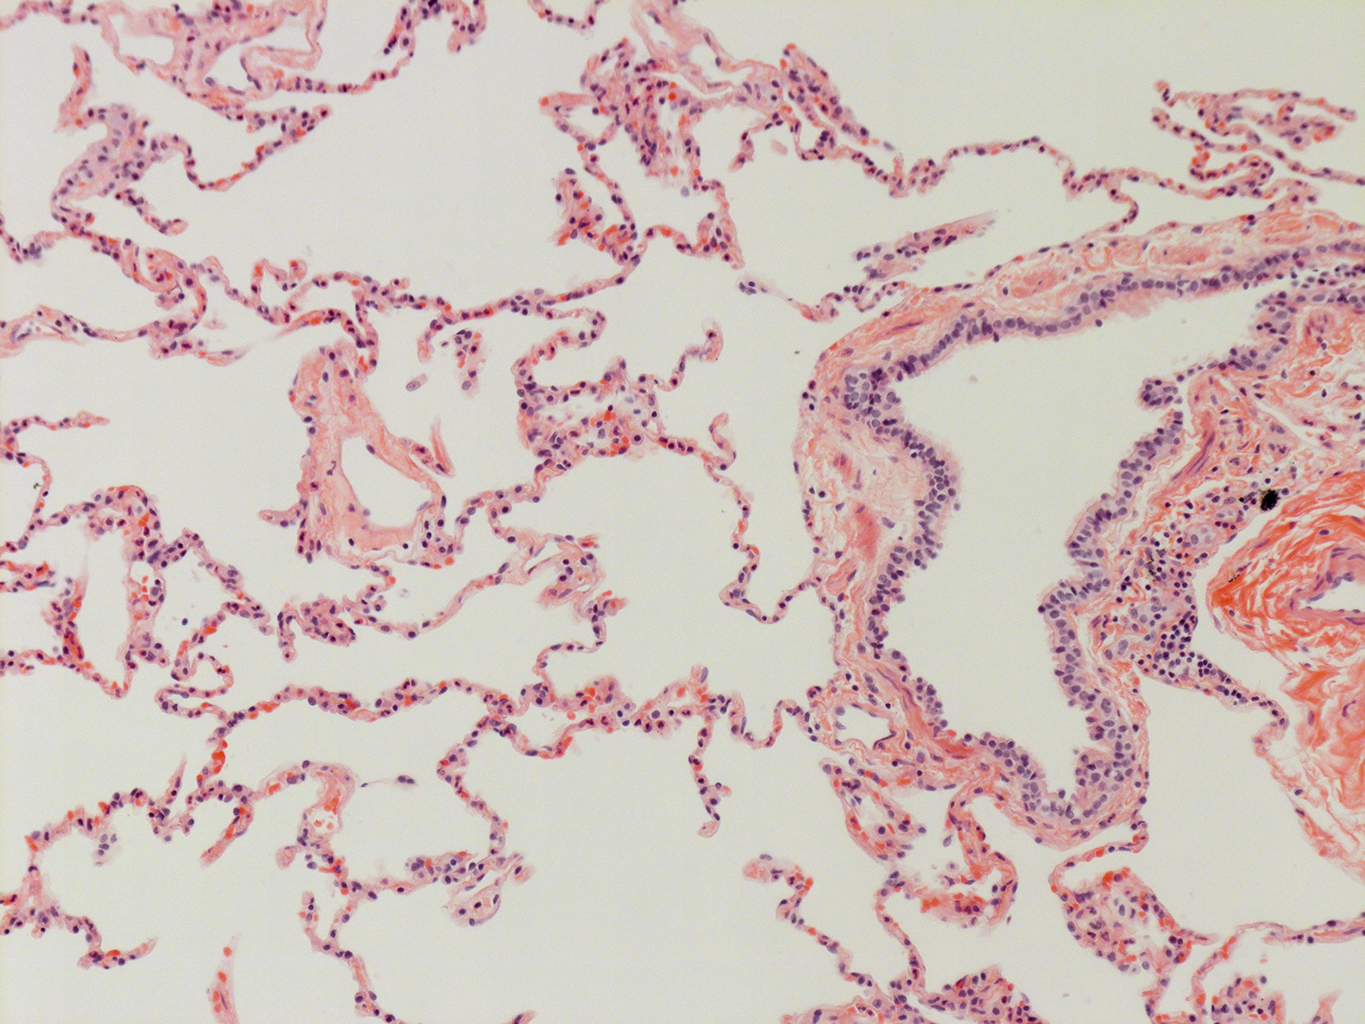

Donor tissue kindly provided by Dr. Scott Randell, University of North Carolina

Tissue Used:

LMHA-15-UNC-2017-12-19_D0037L.05HP_3_48

Gender: Male

Age:Â 43 Year Old

Race: Hispanic

Non-Smoker